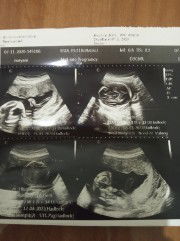

Ijin munduuur y miin,,, debayku udah di surga.. πππ klo liat apliksi ini liat perkmbangan ank π₯Ί